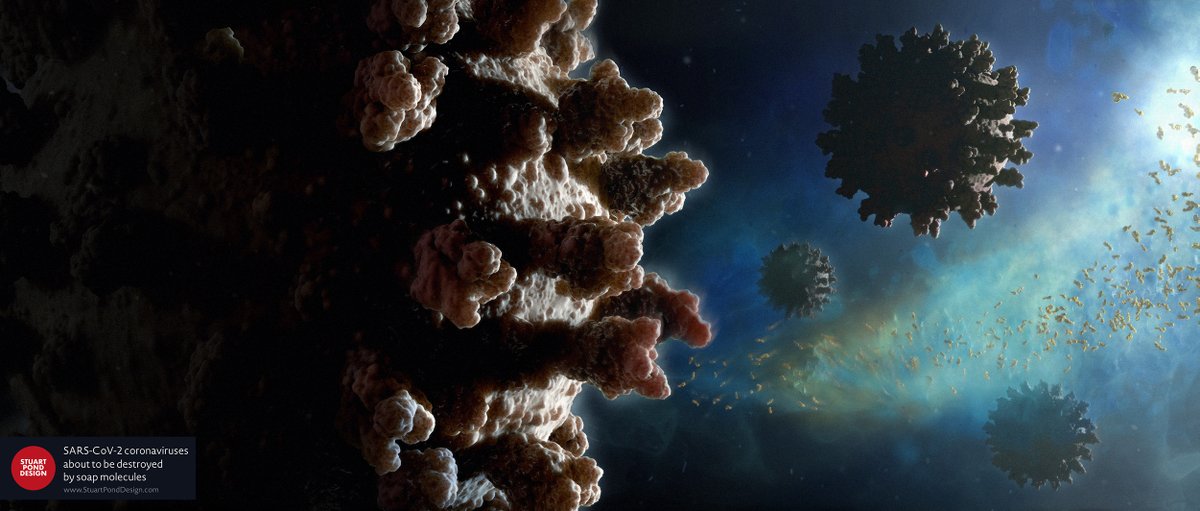

New image created for the day job. SARS-CoV-2 coronaviruses about to be destroyed by soap molecules. Virus models based on structures available at the Protein Data Bank. #ScientificVisualisation

New image created for the day job. SARS-CoV-2 coronaviruses about to be destroyed by soap molecules. Virus models based on structures available at the Protein Data Bank. #ScientificVisualisation